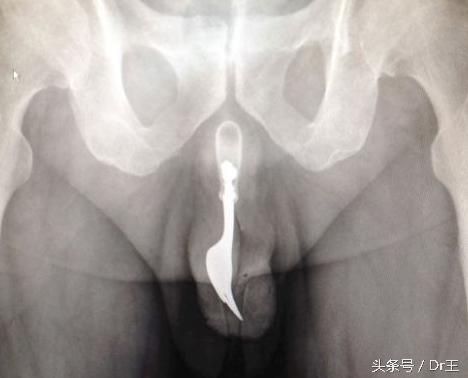

装导尿管多数人心生恐惧

少数人属特殊的尿道恋,多数民众仍无法接受。有时脊椎骨盆受伤、糖尿病严重神经病变,或是动妇科手术时,一听到医师说装导尿管就心生恐惧。当无法自主排尿时,导尿是很重要的治疗方式,虽说会造成些许痛感,但也是有人完全无感。

尿管分为留置导尿管与自我间歇导尿。前者适用于手术过后急性期导尿,但病人较不舒服且容易感染;后者则是长期有导尿需求,如脊椎损伤患者等,必须自行每天导尿4到6次。